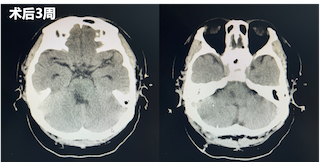

术后一周再次复查CT显示脑干中的血肿明显较前减少。直至三周后,再次复查CT,患者已经没有血肿块,意识较前明显好转,遂转入普通病房继续治疗。在普通病房,患者还同时接受专业的康复训练和中医针灸治疗,患者四肢活动较前好转,目前,已出院至康复医院继续进行康复训练。